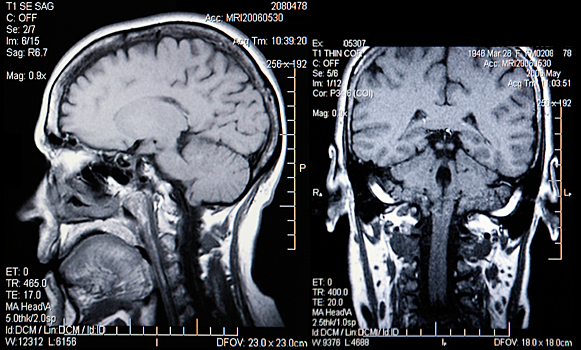

Речь идет о глиобластоме — неизлечимой формы опухоли головного мозга. Открытие опубликовано в статье журнала Autophagy.